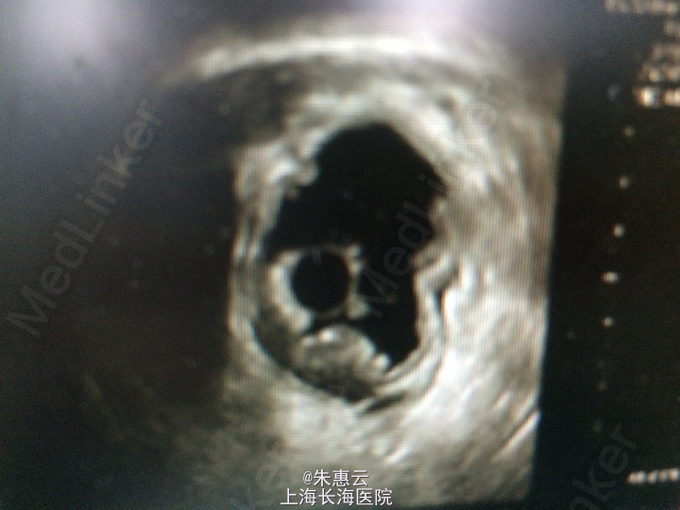

患者,男,61岁 主诉:上腹部不适2月 现病史:因牙痛自服消炎药(具体不详)后,出现上腹部不适,无压痛及放射痛,无发热,无呕血、黑便,就诊于我院行胃镜检查示:胃窦部粘膜隆起性质待查,糜烂性胃炎,十二指肠球部霜斑样溃疡。病理:(胃窦)中度慢性非萎缩性胃炎,HP(+)。超声内镜示:胃粘膜隆起性病变(畸胎瘤可能)。 既往史:2005年及2013年因“胃溃疡”出现黑便,当地医院给与止血、补液等治疗后,患者至今未发黑便。

专科检查:未见明显异常。 辅助检查:胃镜检查示:胃窦部粘膜隆起性质待查,糜烂性胃炎,十二指肠球部霜斑样溃疡。病理:(胃窦)中度慢性非萎缩性胃炎,HP(+)。超声内镜示:胃粘膜隆起性病变(畸胎瘤可能)。 住院期间主要检查结果:血、尿、粪三大常规,肝肾功能电解质、肿瘤指标等未见明显异常。

诊断:胃窦粘膜下隆起 诊疗经过:入院后行胃ESD术,术中于粘膜隆起区下方见较大溃疡,结合患者HP(+),故先行抗HP治疗。